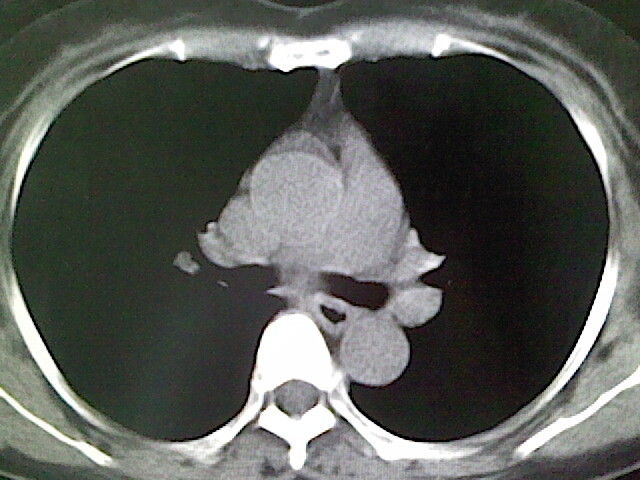

女,52岁,咳嗽,咳痰多日

左下肺陈旧纤维索条!

左肺舌段炎性改变

我见过几例,为炎症后纤维条索

慢性炎症后改变

考虑慢性炎性病灶粘连牵拉改变。

左肺舌叶纤维锁条病变。

左肺上叶下舌段炎症并局部胸膜反应。

左肺舌叶纤维索条影。

左肺舌叶段陈旧性病变

左肺舌段炎性反应。片子的质量太不好了。

左肺舌段炎性

炎性改变

左肺舌叶纤维索条影